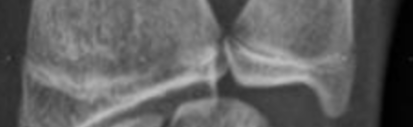

el plakları gitti diz ve omurgadan boy atmayı umacağım muhtemelen el plaklarının kapanmasına 3 4 ay kaldı

evet kemik yaşı cope dedik ettik ama dizlerdeki plaklar kemik yaşı 17 olduğunda c2-c3 safhasına geçip kapanıyor ama bende 15likken kapanmış so brutal.

Evet kemik yaşı copedir. Gigantismli hastaların kemik yaşı 16 yaşındayken 18-19 a ulaşır ki buna füzyon diyemeyiz. Esas epifiz kapanması kemiklerin içindeki kondrositlerin olgunlaşmasıyla olur. Yani kemik yaşı adli vakalarda kimliği belirsiz kişilerin kimliğini belirlemek için kullanılan bir şeydir gelecekteki boyunuzu tahmin etmek için kullanılabileceğinin kesinliği veya net bir delili yoktur. Zaten 1.5 yıl kadar sapma söz konusu olabiliyor.

bide bazı nadir durumlarda kemik yasınla plak acıklıgı uyusmayablir imkansız degil aq

XRAYLER HİÇBİR ZAMAN MRLAR KADAR GÜVENİLİR OLMAYACAK VE MR ÇEKİMLERİ İLE XRAYLERDEKİ MİLİMETRİK HESAPLAR ARASINDA %20 BİLE FARK OLABİLİYOR.